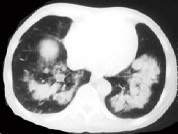

单项选择题女,34岁, 新月体肾炎患者,最近咳嗽咯血, 第一次行胸片检查考虑为双下肺感染,抗感染治疗后无明显好转, 症状加重,4天后复查并行CT检查如图, 应考虑为 ( )

D、肺出血肾炎综合征